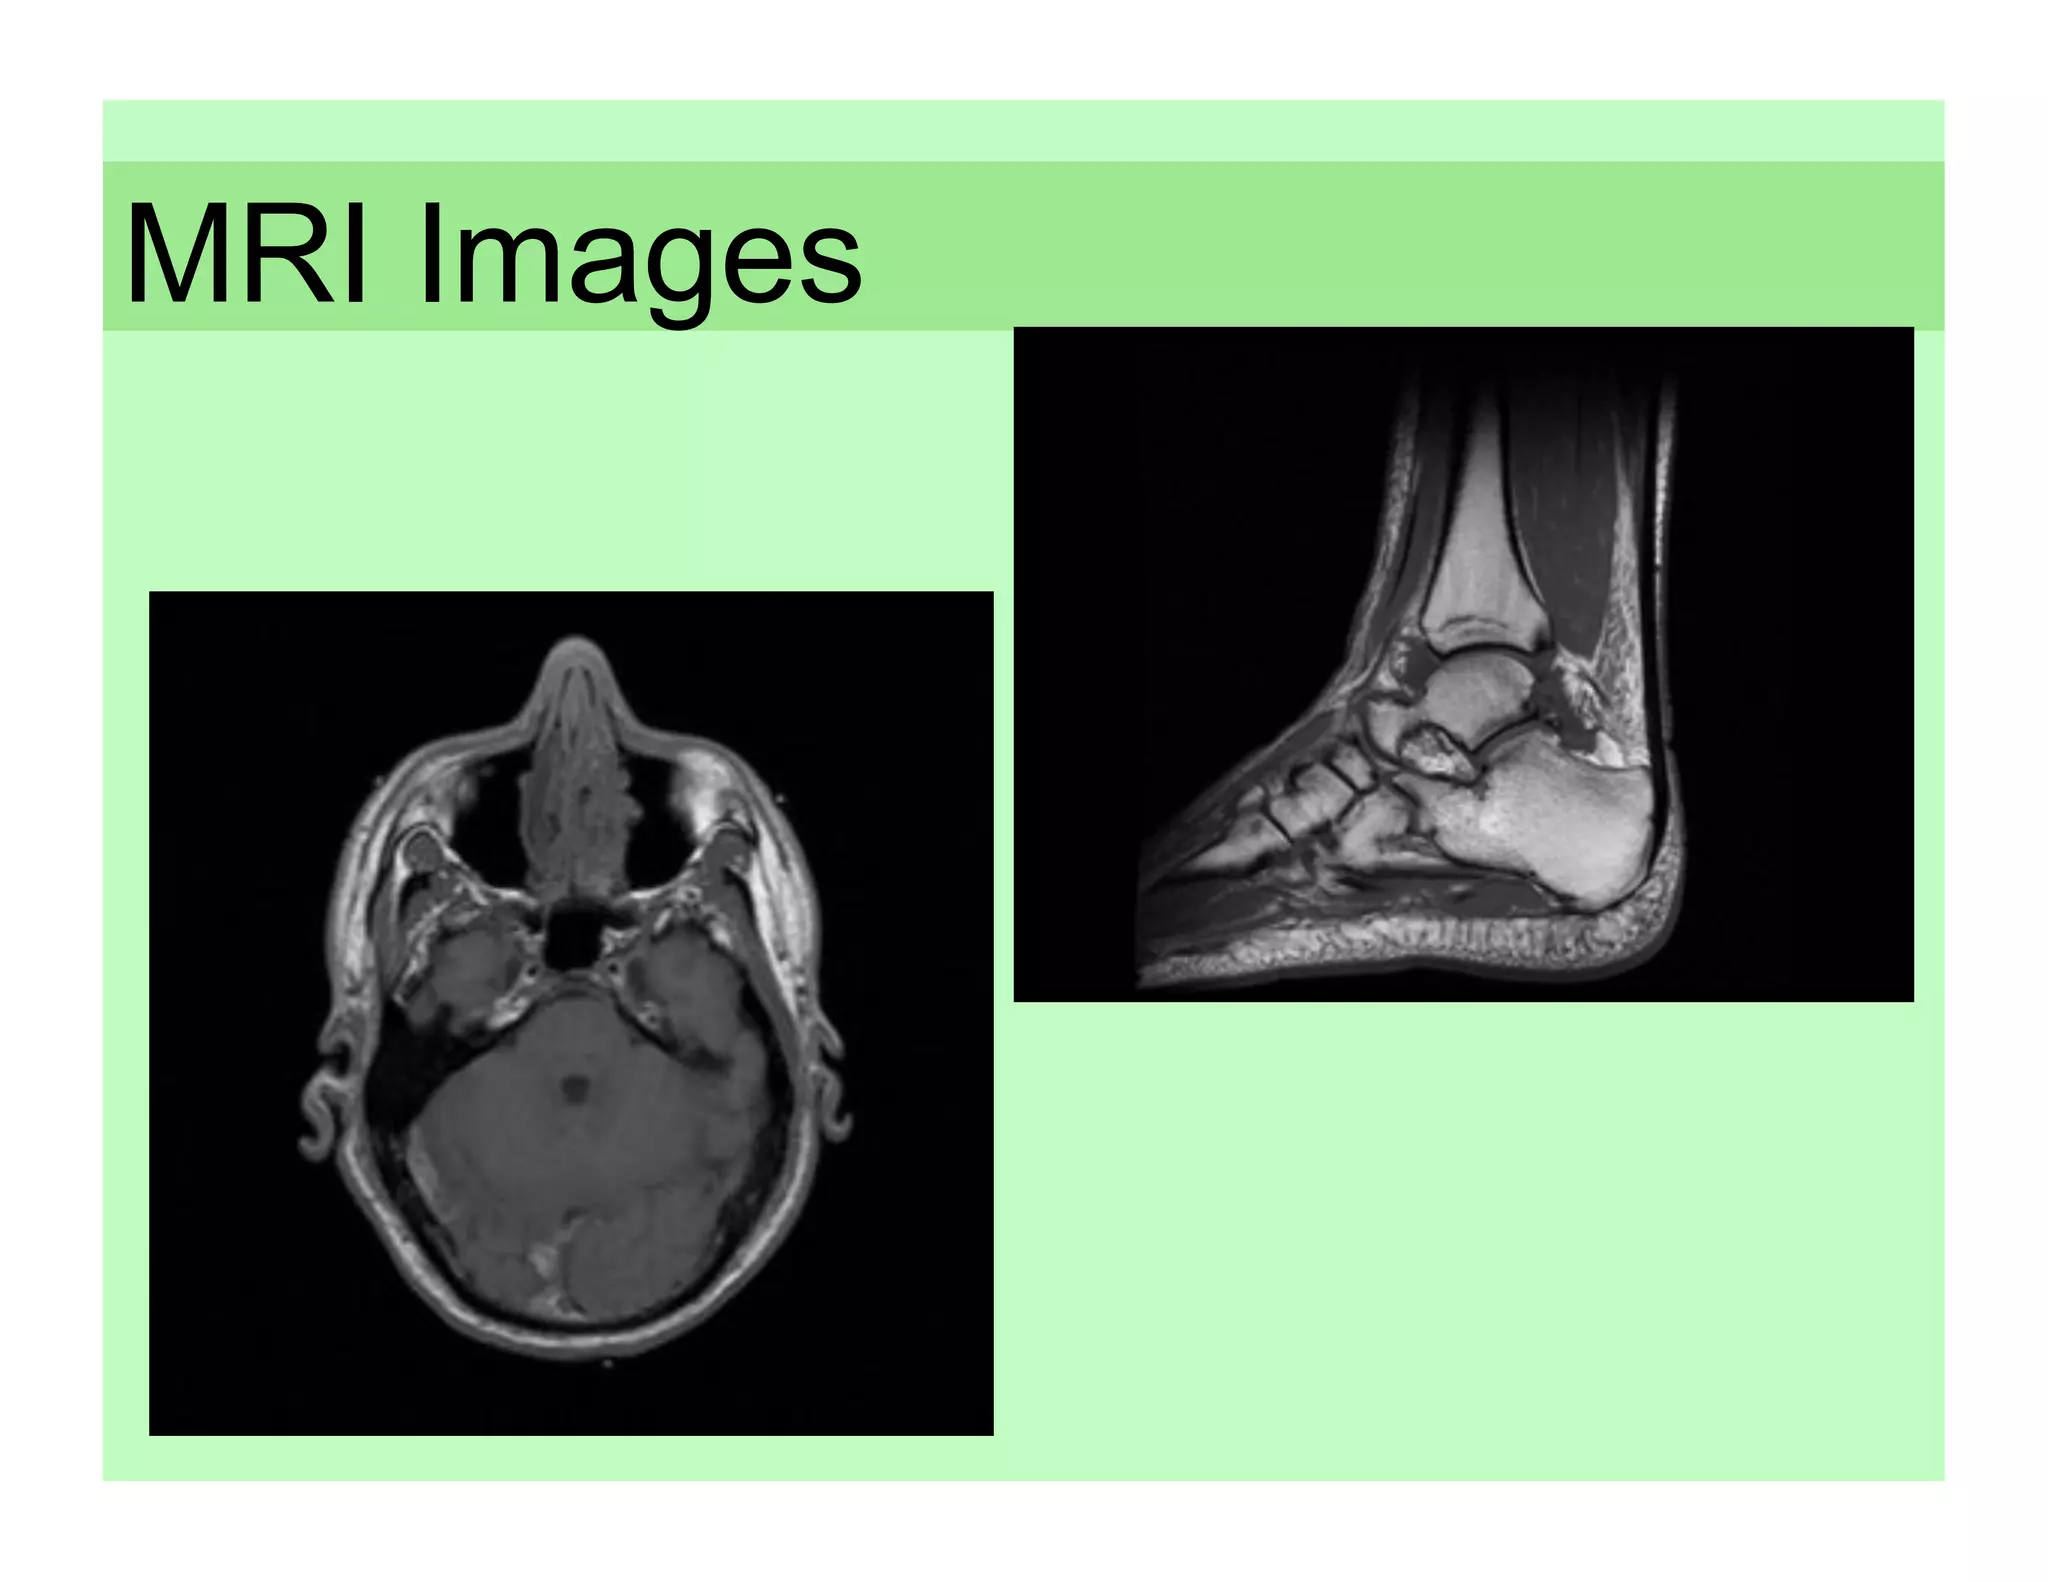

MRI Images

M R I MagneticResonance Imaging Developed in the early 1980s, MRI technology does not use harmful x-rays to generate an image of internal structures. MRIs produce detailed internal images of bone, soft tissue, blood vessels and muscles.

How MRIs work… •  Radio waves, stronger than the magnetic field of the earth, are sent through the body The water in cells is the source •  The radio waves disrupts of radio waves in most tissues. the nuclei of atoms The waves are captured and causing them to emit their translated into an image by a own radio waves computer.